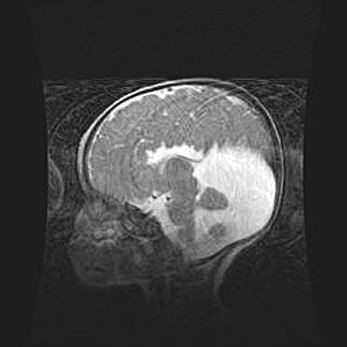

Мальформация Денди-Уокера. Киста задней черепной ямки.

Агенезия мозолистого тела.

Возраст: 2,5 месяца

Вес: 2420 г

Пол: женский

Окружность головы: 37 см

Срок гестации: 32 недели

Мальформация Денди—Уокера — редкий вид патологии ЦНС, представляющий собой врожденный порок развития каудального отдела ствола и червя мозжечка, ведущий к неполному раскрытию срединной (Мажанди) и латеральных (Лушка) апертур IV желудочка мозга. Для этогно синдрома характерна триада симптомов: гипотрофия червя мозжечка и/или полушарий мозжечка, кисты задней черепной ямки, гидроцефалия различной степени. В 70% случаев порок сочетается и с другими аномалиями головного мозга, в частности с агенезией мозолистого тела.